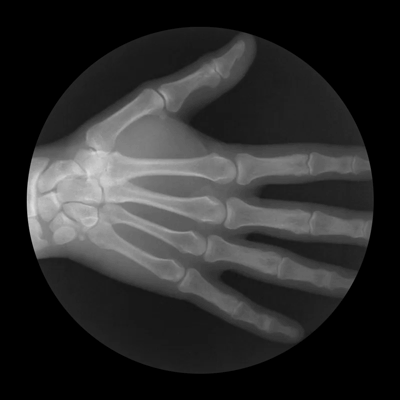

Hand